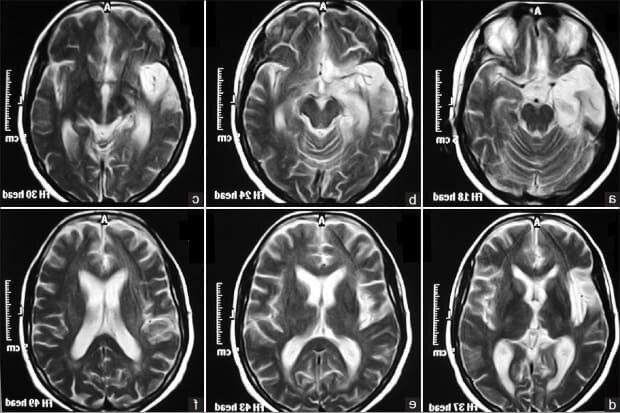

Диагностика болезни включает в себя использование различных методов, таких как нейропсихологические тесты, электроэнцефалограмма и магнитно-резонансная томография головного мозга. Классификация болезни основана на состоянии кровообращения в головной области и наличии нарушенного артериального давления.

Первая стадия болезни характеризуется нарушениями мозгового кровообращения и может проявляться неврологическими симптомами, такими как головные боли, головокружение и шум в ушах. Для подтверждения диагноза можно использовать методы обследования, такие как энцефалография, КТ или МРТ мозга.

Во второй стадии болезни наблюдается умеренное нарушение мозгового кровообращения и симптоматика становится более выраженной. В этом случае, для диагностики можно использовать УЗИ сосудов головы и шеи, а также допплерографию.

Третья стадия характеризуется значительным нарушением мозгового кровообращения и возникают серьезные неврологические симптомы. Для подтверждения диагноза врач может назначить компьютерную ангиографию или церебральную ангиографию.